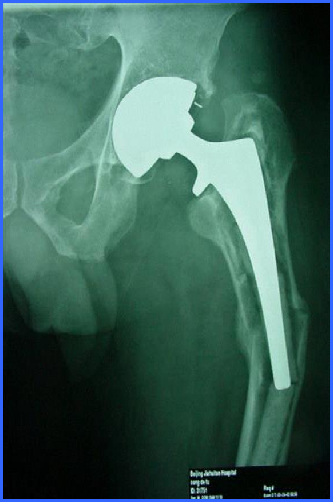

髓内固定:(二)翻修术

①适应征:假体松动的骨折

②原则:

尽可能的保留骨量

尽可能使假体与完整的宿主骨之间获得牢固固定

③假体的选择

长柄远端固定非骨水泥型

假体的长度至少要超过骨折端两倍于股骨直径的距离

骨缺损者,联合异体皮质骨板髓外固定

④对于骨量丢失严重、无法重建的病人:

异体骨假体复合物:适用于年轻的病人,此法可保留软组织和肌肉止点

肿瘤型假体:适用于老年病人,使病人早期负重活动